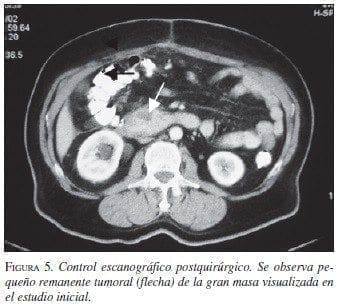

Paciente 4: Hombre de 63 años de edad, con cuadro clínico de sensación de masa abdominal, dolor y vómito. La TAC abdominal preoperatoria mostró gran masa retroperitoneal (figura 4). La sofagogastroduodenoscopia informó compresión extrínseca de la segunda y tercera porción duodenal; las biopsias mucosas fueron negativas para malig-nidad. En septiembre de 2002 se llevó a cirugía y se practicó resección de la masa, colectomía derecha e ileotransversostomía término-lateral; quedó con tu-mor residual en un volumen aproximado de 2% ad-herido a la cabeza del páncreas. Por riesgo quirúrgico del paciente (enfermedad cardiovascular y enfermedad pulmonar obstructiva crónica) no se consideró pertinente extender la resección a una pancreatoduodenectomía. La patología informó TEGI, sin invasión a colon. La IMHQ confirmó el diagnóstico (cuadro 1. En el postoperatorio inme-diato cursó con infarto agudo del miocardio, que requirió angioplastia de urgencia, con evolución adecuada. Se encuentra en tratamiento con imatinib, sin evidencia de crecimiento tumoral por escanografía (figura 5).